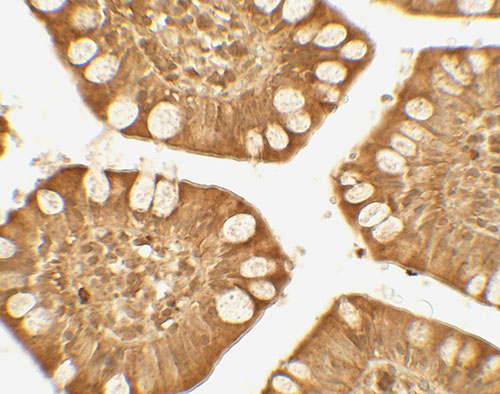

Immunohistochemistry of TRIM21 in human small intestine tissue with TRIM21 antibody at 5 μg/mL.